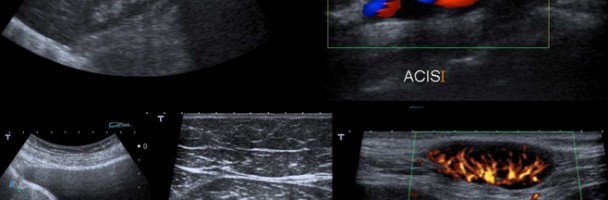

L’esame ecografico è l’esame di prima istanza nella valutazione delle strutture non contenenti aria (es. polmone) o non circondate da aria e da osso.

Sebbene l’ecografia sia utilizzata, prevalentemente, appoggiando la sonda sulla superficie esterna del corpo, talora è necessario introdurla all’interno per studiare organi che sarebbero mal distinguibili da fuori.

Per questo sono state disegnate sonde di forma adatta per essere messe nella cavità rettale, attraverso l’ano, al fine di indagare la prostata e le pareti dell’ultima parte dell’intestino (Ecografia Trans-rettale) o, nella vagina (Trans-vaginale), per esplorare l’apparato genitale femminile.

Con l’ecografia, associata alla tecnica doppler , si può esaminare il flusso del sangue nel cuore e nei vasi.

Un fascio d’ultrasuoni che colpisce un liquido che scorre in un vaso può far capire la direzione e la velocità del flusso.

Mettendo insieme l’ecografia ed il doppler è possibile osservare non solo le eventuali modificazioni della forma del cuore, delle arterie e delle vene, ma anche le caratteristiche del flusso del sangue al loro interno.